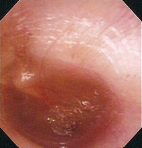

Acute Otitis Media (Bullae in Eardrum) Aged 7, female

Before paracentesis

6th day after paracentesis

Comment:

Views on the 2nd day after onset of acute left otitis media. NBI enhanced visualization of deeper vessels.

After paracentesis, NBI could still enhance visualization of deeper vessels thus another incision was required.

Images and comments by Dr. S. Takano <ENF-V2>